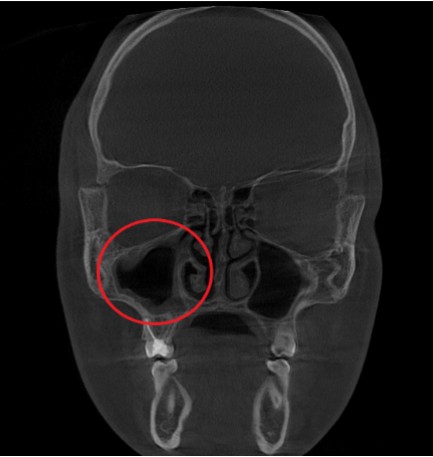

Проведена компьютерная томография околоносовых пазух, которая подтвердила наличие правостороннего гемисинусита (воспаление нескольких пазух с одной стороны), как следствие периодонтита зуба 1.6.

Представлено КЛКТ околоносовых пазух до начала лечения. Выделена зона воспаления пазух.